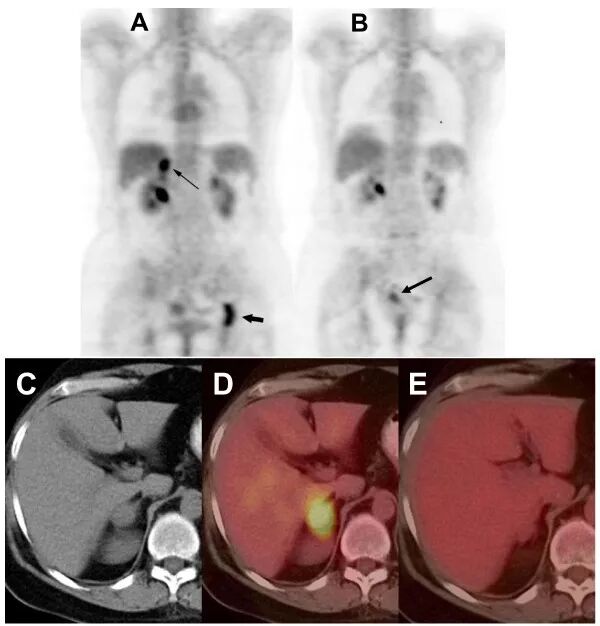

72名患者的CT扫描显示疾病控制率为97%,其中40%的患者有部分反应,57%的患者病情稳定,3%的患者病情进展。中位无进展生存期为7.6个月。